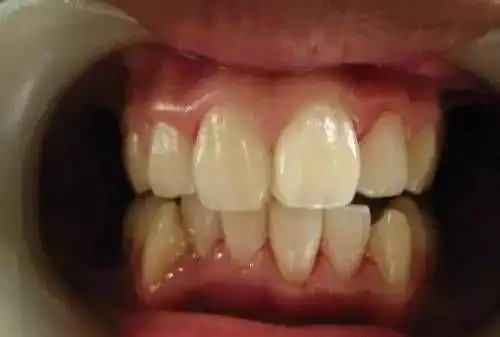

一个高职学校的学生,口腔内严重的牙结石,可能小时候没有刷过牙

洗牙(洁治)后效果很明显